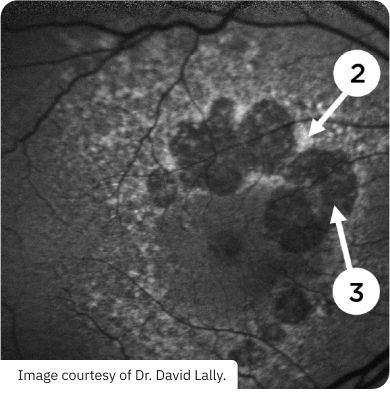

Fundus Autofluorescence (FAF)

faf-2

Advanced AMD (GA)

Key Features1,7

(1) Reticular pseudodrusen appearing as multiple, clustered, regularly networked, round areas of low-contrast hypo-autofluorescence may be prognostic of advancing AMD

(2) Areas of hypo-autofluorescence with sharply demarcated borders indicate atrophic lesions

(3) Abnormal patterns of hyperautofluorescence surrounding atrophic lesions